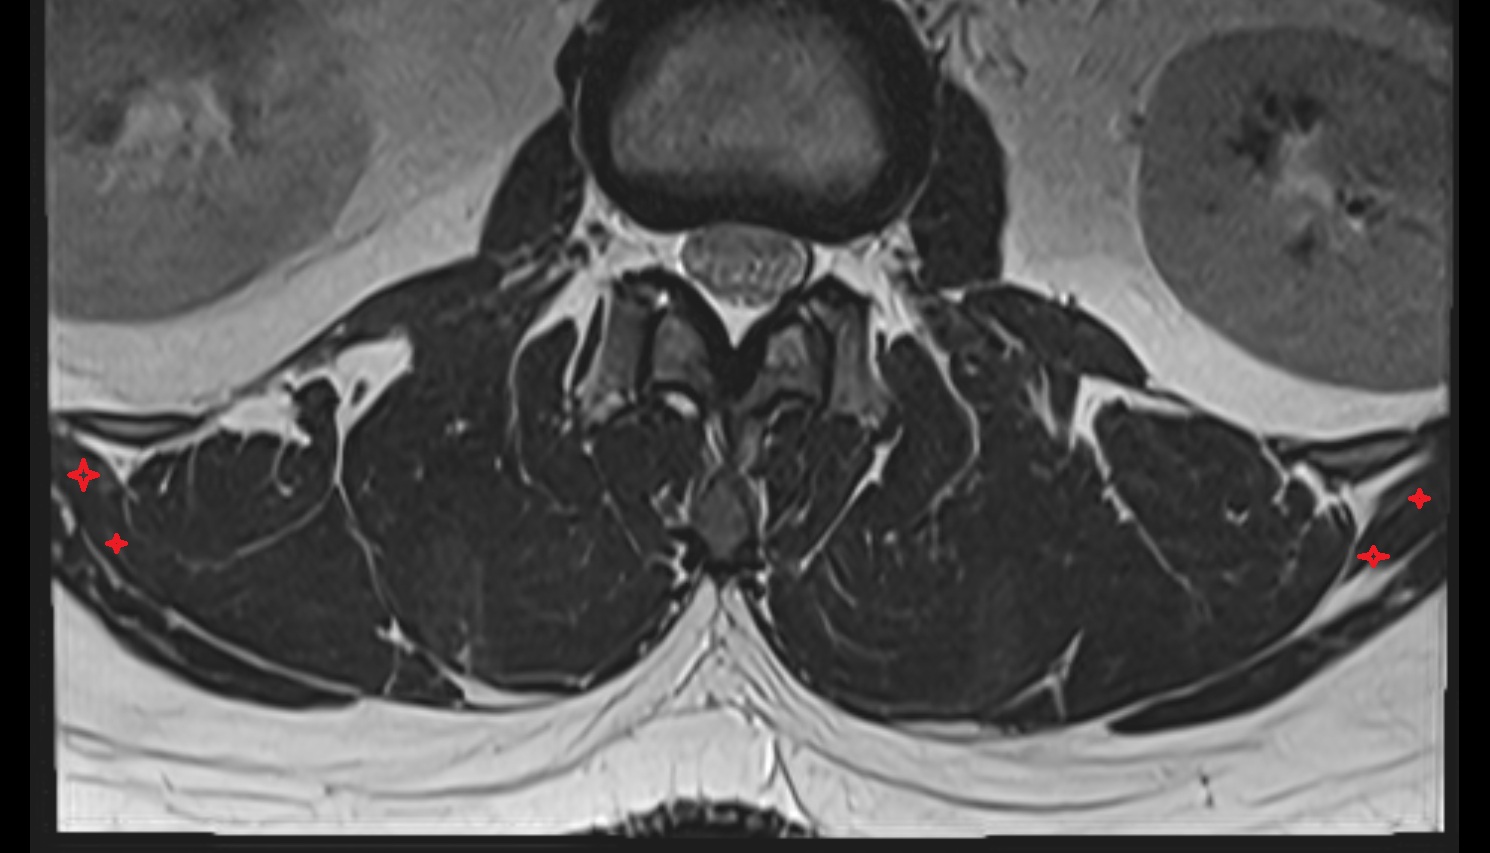

- Cauda equina

- Conus medullaris